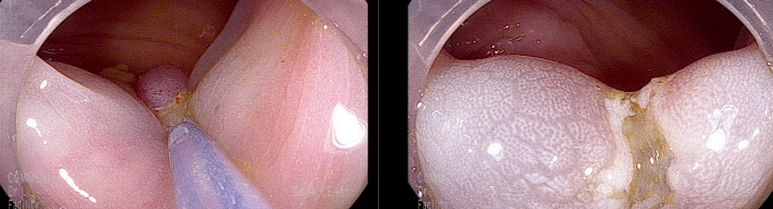

마지막 유경성 거대 용종을 제외하고 점막 소구 패턴(pit pattern)이 불규칙하게 관찰되어(Vi) 고등급의 선종 혹은 점막암을 의심하여 충분히 융기시켜 경계가 확실히 포함되고 한조각으로 완전 절제하기 위해 넓게 절제함

19-20 mm 크기의 유경성(목이있는) 용종은 클립을 적절히 사용하여 출혈예방함